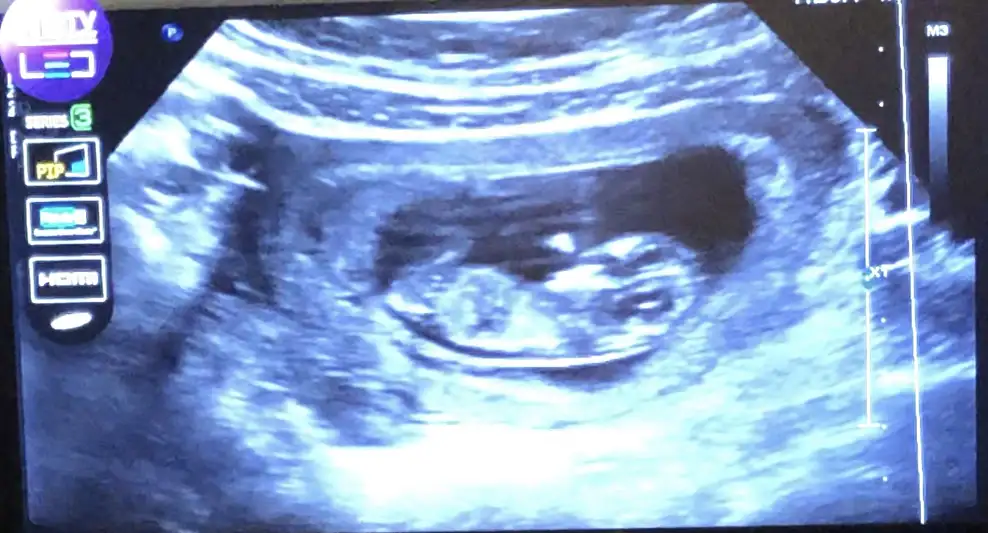

dr soylemeden siz gorun genital nub teorisi ( bebegin cinsiyeti)

Geçen hafta gitmiştim dr %80 kız demişti ama degişeblr dedi şmdi sizde böyle söylynce kadam karıştı 🧐